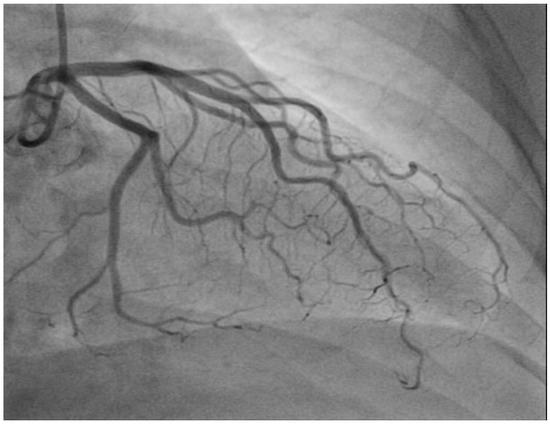

In May 2018, the patient received the second cycle of nivolumab plus ipilimumab. However, two weeks later, the patient was admitted to the Department of Internal Medicine with chest pain, fever (38.7 °C), and dyspnea. Further evaluation, including electrocardiography and an angiogram of the coronary arteries, revealed no evidence of pathological findings (Figure 2). An echocardiogram showed normal LV systolic function with an ejection fraction of 65% and signs of impaired LV relaxation and mild mitral regurgitation, with no additional pathological findings.

Figure 2. Electrocardiography, angiogram of the coronary arteries showing no pathological findings.